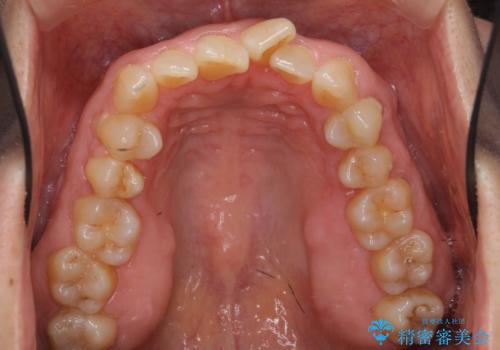

- 前歯のがたつきを主訴に来院。

右下の犬歯が歯ぐきが痩せて、歯肉退縮しておりそれを抜歯しました。

上の前歯はIPRを行なっています。